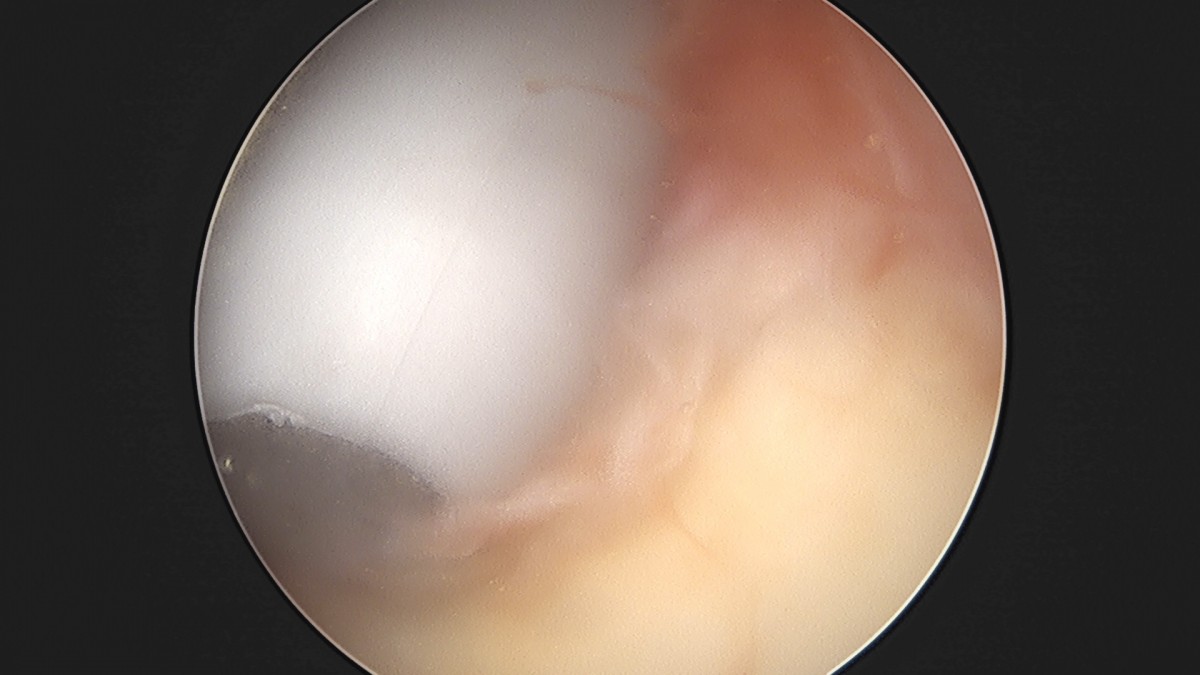

이재상원장님 어깨 견봉하 감압술 및 관절낭 이완술 양명O 환자

dae765e4d9ac96aee867c9d6292d8784_1758004380_8605.jpg